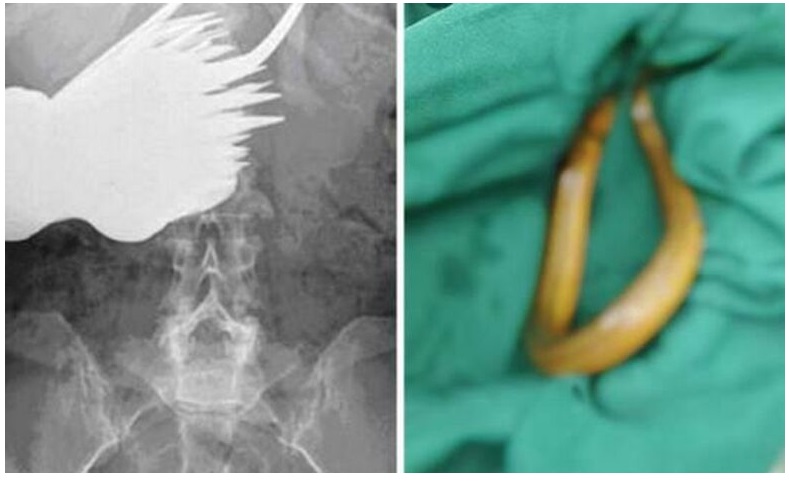

一个可疑的故事 这条 15 英寸的鳗鱼是从一名中年男子的腹部拉出来的

2020 年,一名男子因感染性休克入院后,医生从他的结肠中取出了一条 15 英寸长的亚洲沼泽鳗鱼。

他说他通过**将它仍然活着插入他的身体,以“治愈他的便秘”。